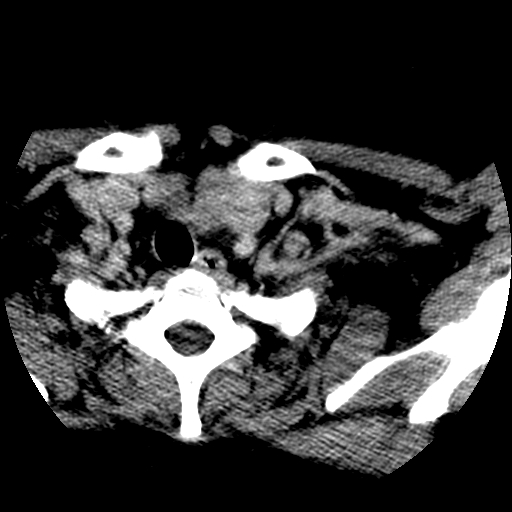

标题: CT25491:女,55岁,发现左侧甲状腺肿块一个月。 [打印本页]

标题: CT25491:女,55岁,发现左侧甲状腺肿块一个月。

女,55岁,发现左侧甲状腺肿块一个月,彩超示:甲状腺多发结节伴左叶结节液化。

左右叶都有,峡部也受累,有钙化,考虑结甲可能性大。

考虑右叶结节性甲状腺肿,伴左叶钙化。主要(1)密度均匀,边境清。(2)病灶与血管界限清。

边界清,无明显强化,考虑考虑甲状腺腺瘤